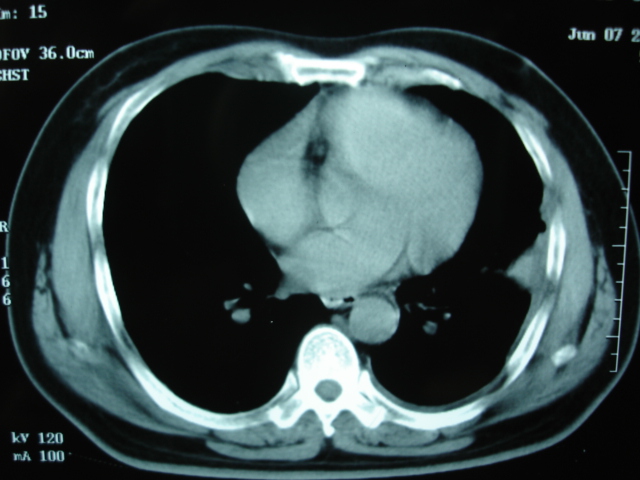

2009.6.4 2009.6.7 2009.8.21

第二次ct2009.6.7 住院后ect未见异常,查痰(阴性)大量抗菌素抗炎一个月后病灶明显变小,7月5号出院后回家后口服抗菌素45天